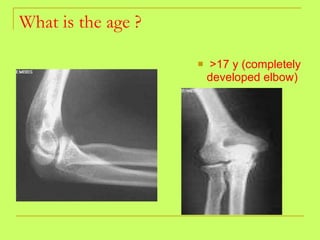

Age from upper limb examination 1)At the wrist and shoulder joint (lower ends of radius and ulna and head of the humerus) 19-20  years. 2) At the elbow region: trochlea and capitulum  (14 years)- trochlea and capitulum + lower end of the humerus  (15years) 3)Lat.epicondyle and head of  ulna(17 years). 4)Med epicondyles and the head of the radius  (18years) 5)Metacarpals and phalanges  (16 y in females and 18 years in males).

What is the age ? >17 y (completely developed elbow)